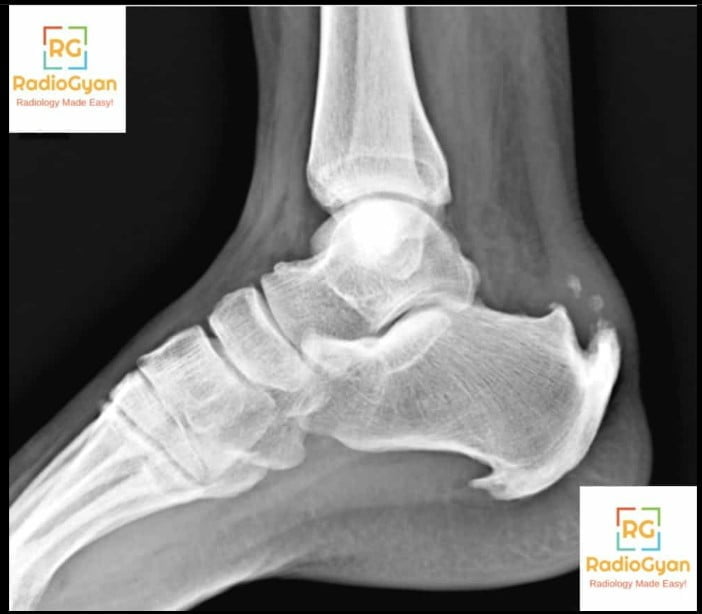

This bony prominence, known as Haglundโs deformity, results from abnormal enlargement of the posterosuperior aspect of the calcaneus at the site of Achilles tendon insertion. On lateral heel radiographs, this conspicuous exostosis is clearly visualized and often leads to mechanical irritation of the adjacent retrocalcaneal bursa and Achilles tendon, causing painful inflammation termed Haglundโs syndrome. Clinical features include posterior heel pain, swelling, and tenderness often aggravated by rigid or high-heeled footwear. The deformity may be associated with conditions such as Achilles tendinopathy, retrocalcaneal bursitis, and insertional Achilles tendon degeneration.

The abnormal bony prominence causes repetitive friction and impingement against the retrocalcaneal bursa and Achilles tendon during ankle motion and weight-bearing, especially in patients wearing rigid shoes. This mechanical irritation induces inflammatory changes including bursitis and tendon degeneration or partial tearing. Over time, chronic inflammation may lead to thickening and fibrosis of the bursa and Achilles tendon insertion, creating pain and functional impairment.